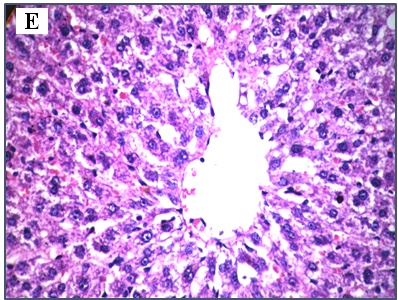

The results of Eosin & Heamtotoxylen stain of sections of liver rat in fig. 1. showing healthy hepatic parenchyma in the control group while, in VPA group massive vacuolar degeneration of hepatocytes together with dilated and congested blood sinusoids were appeared. B-V group showing dilated blood sinusoids with atrophied hepatic cord. (L-V) group showing swollen hepatocytes with faint cytoplasm. (B-L-V) group apparently healthy hepatic parenchyma as the control group.

Fig. 1: Photomicrograph of rat liver sections showing control group (A) apparently healthy hepatic parenchyma (H&E X= 400). Massive vacuolar degeneration of hepatocytes together with dilated and congested blood sinusoids in VPA group (B) (H&E X 400). Dilated blood sinusoids (arrow head) with atrophied hepatic cord in B-V group (C) (H&E X= 400). (L-V) group (D) showing swollen hepatocytes with faint cytoplasm (H&E X 400). (B-L-V) group (E) apparently healthy hepatic parenchyma (H&E X= 400)